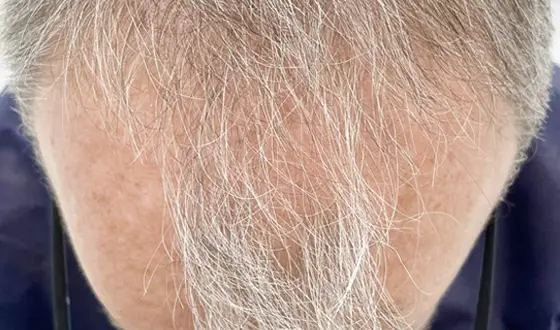

Plasma Rico em Plaquetas de 5 sessões

Após 6 meses

Após 6 meses

Plasma Rico em Plaquetas de 3 sessões